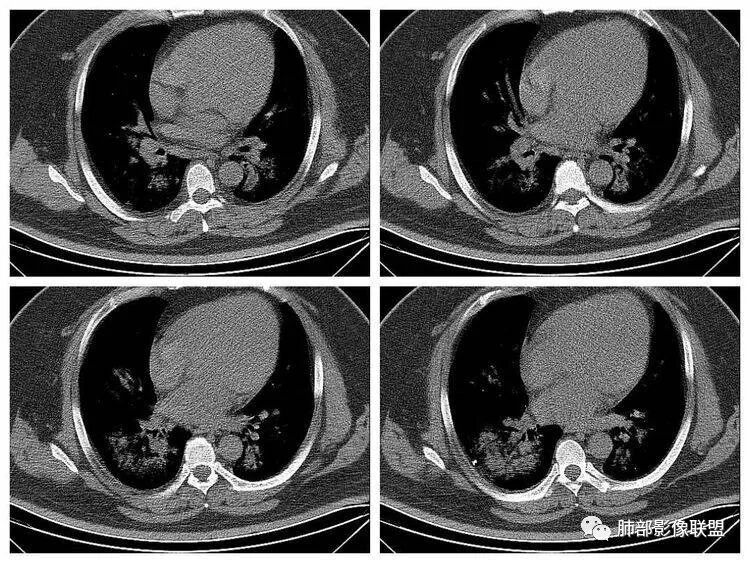

长沟流月去无声:第三点有意见这个人心脏大,左室供血很不好

南边:南边:不大啊冬瓜:熊老师不会考虑病毒感染,爆发性心肌炎吧南边:这个就不敢说淘时光:左心室心腔饱满,室间隔向右室侧有些移位,感觉左室有增大

长沟流月去无声:这个左室心肌都薄了南边:没有做增强啊长沟流月去无声:可以提示大家去看一下流感病毒性肺炎重症,WHO和卫生部都出过指南,建议你们仔细看看指南里危险人群一节,是哪几个

南边:1、感染:间质分布——病毒、支原体,支原体一般树芽征明显,累及小气道多,而且临床轻,不太支持2、血管炎,需要相关病史3、肺水肿:心脏不大,无胸水、无中央间质增厚、小叶间隔增厚,不太支持4、PAP,病史影像表现都不支持初学者:可能是病毒,但是好像并不是我们常见的流感病毒实变为主,腺病毒?就是太多灶了一点